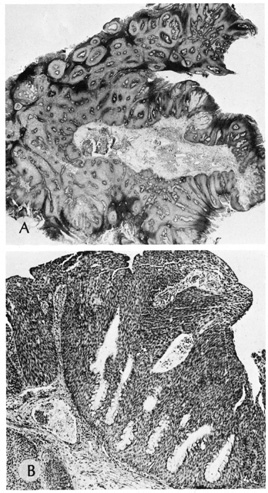

Verruca vulgaris (warts) are caused by a variety of papilloma viruses and may present as small papules with a digitated surface or elongated filiform warts around the eyes. Histologically, they demonstrate varying degrees of massive papillomatosis, hyperkeratosis, and acanthosis with parakeratosis and collections of serum in the stratum corneum at the tips of the digitations (Fig. 8). In early warts, the keratinocytes in the granular layer and just beneath the granular layer are vacuolated with condensation and clumping of dark-staining keratohyaline granules and occasional eosinophilic inclusion bodies in the nuclei.

Fig. 8. Verruca Vulgaris—A. Low-power photomicrograph illustrating papillomatous growth with a fibrovascular core, hyperkeratosis, and acanthosis (hematoxylin and eosin stain). B. High-power photomicrograph demonstrating intranuclear viral inclusion (black arrow) (hematoxylin and eosin stain). (Photos courtesy of William Morris, M.D.)